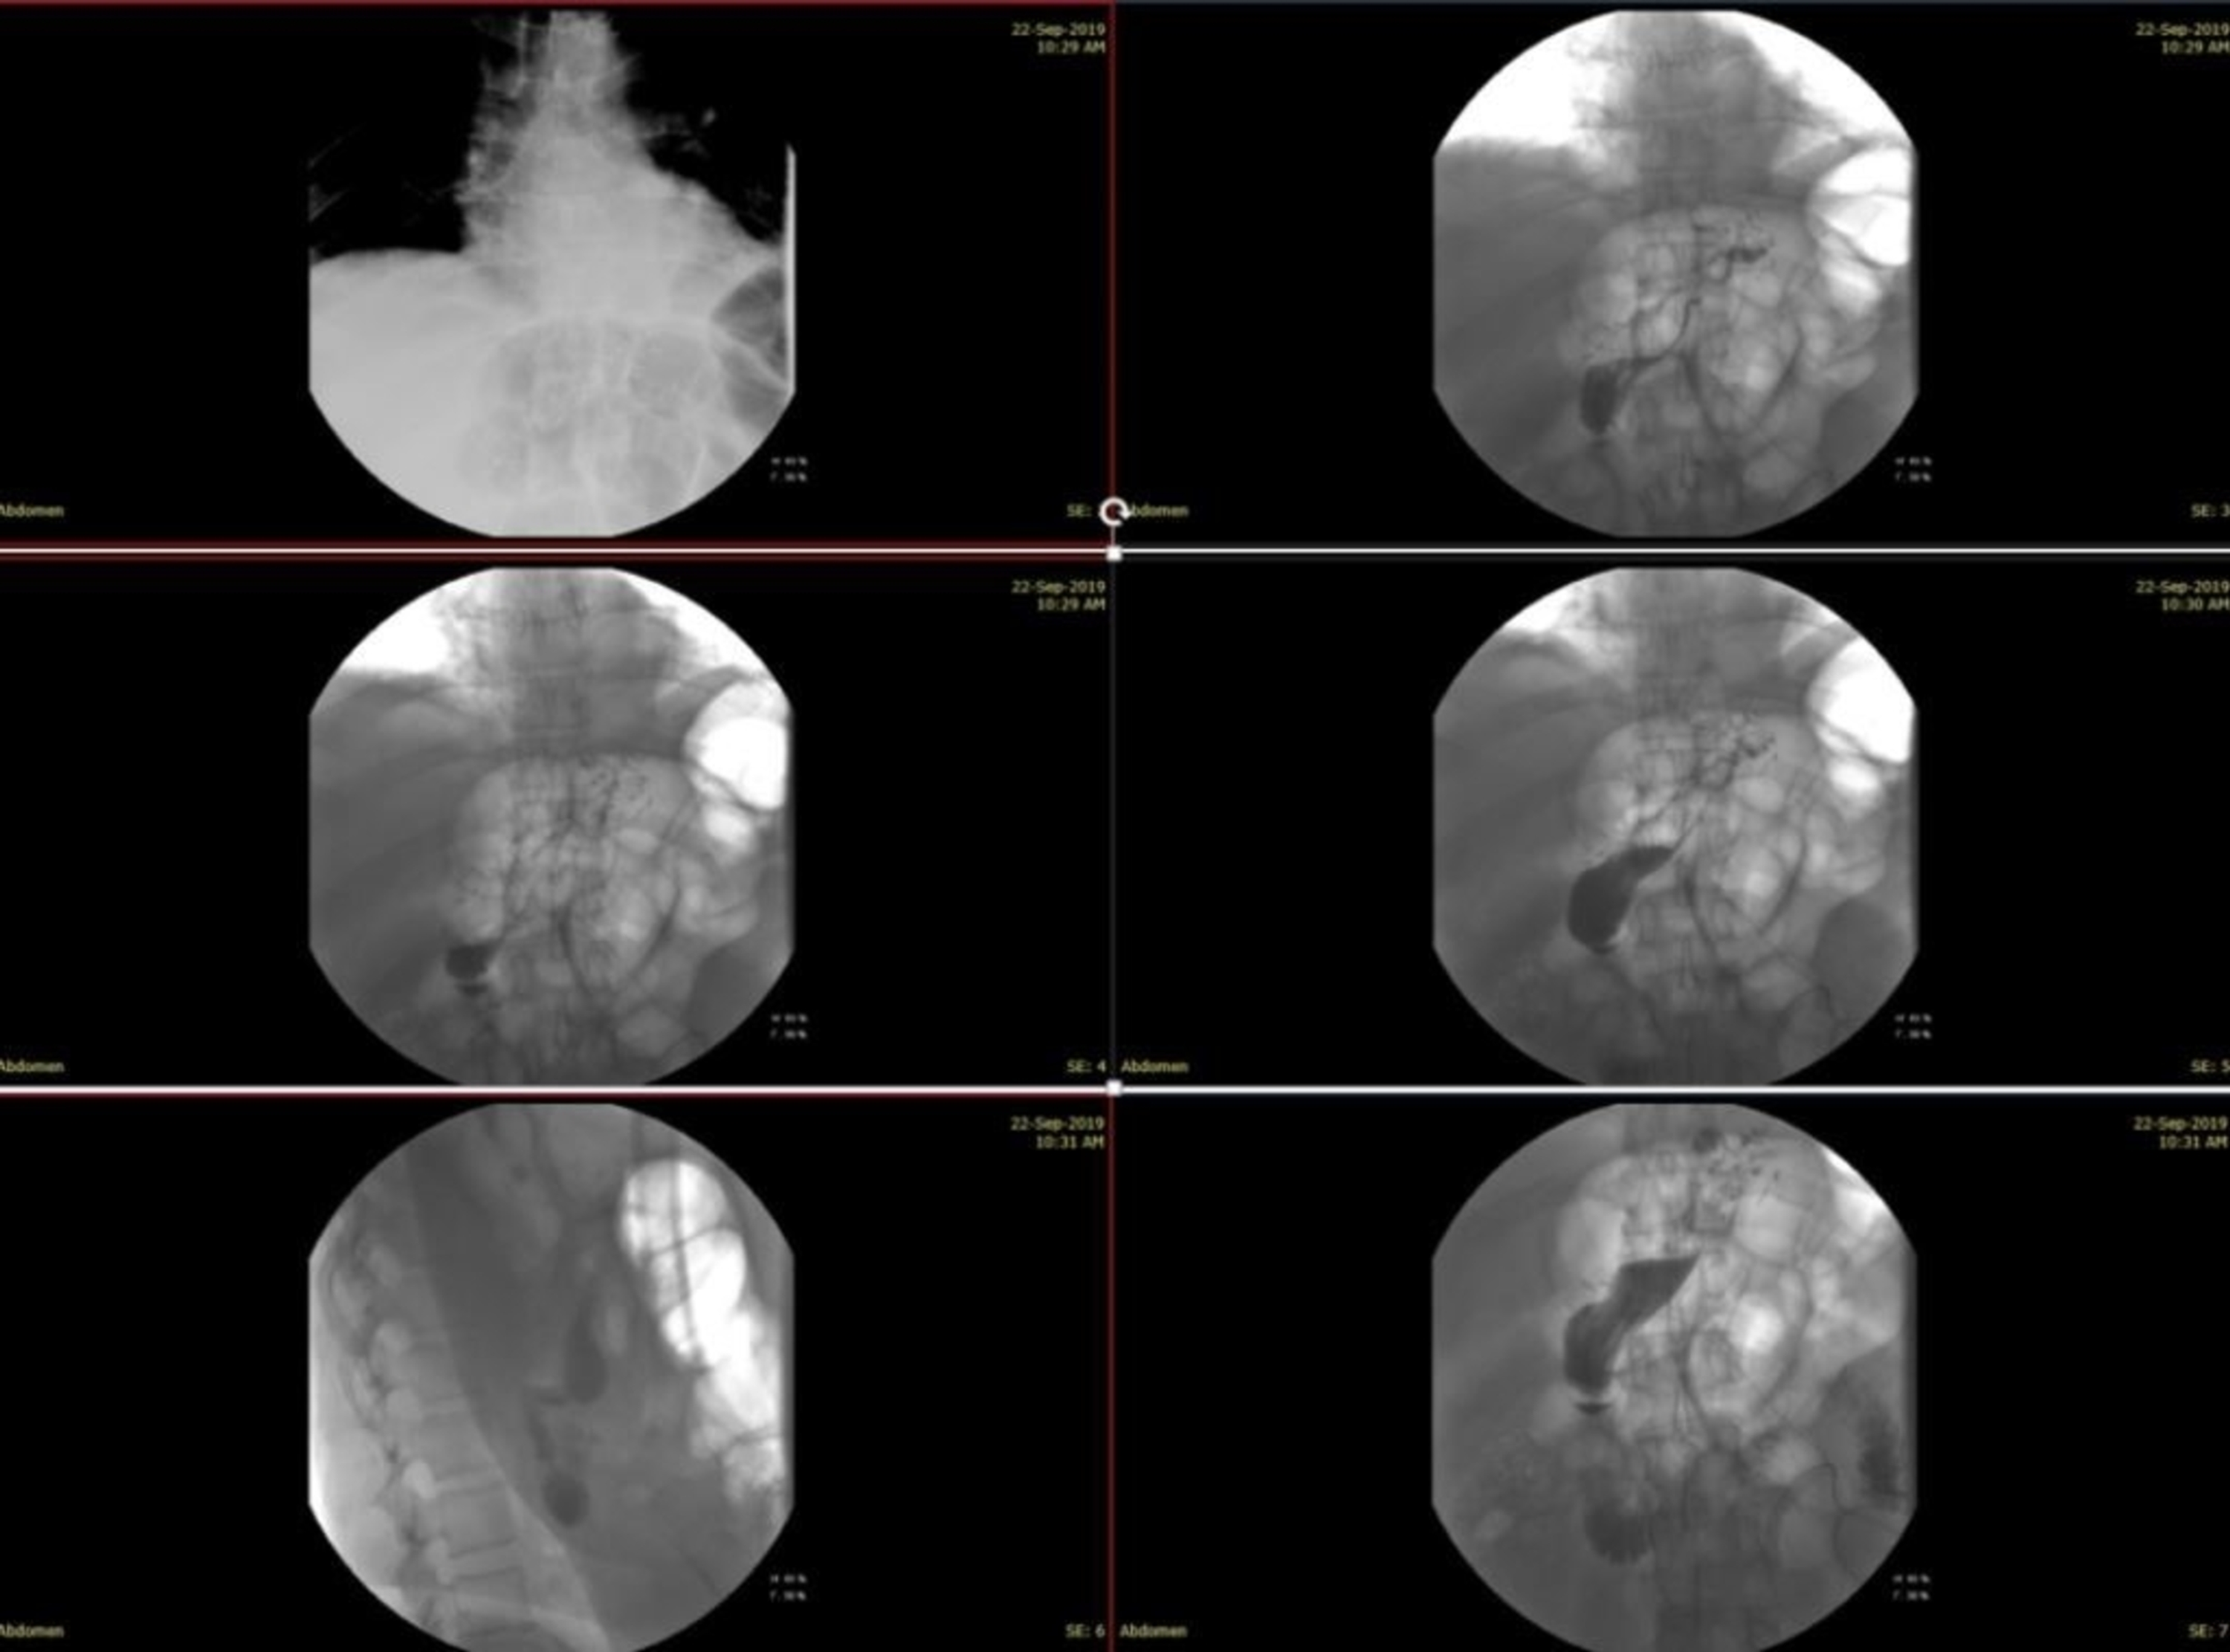

From www.researchgate.net

Upper GI series revealing gastric leak. Download Scientific Diagram Sleeve Gastrectomy Leak Symptoms Physical symptoms of a gastrointestinal leak after gastric sleeve surgery include: They can be anastomotic or staple line. In our review, we noticed that the most important clinical sign or symptom in. If you have had weight loss surgery to remove part of your stomach, also known as a gastric sleeve, you must know the signs and symptoms of a. Sleeve Gastrectomy Leak Symptoms.